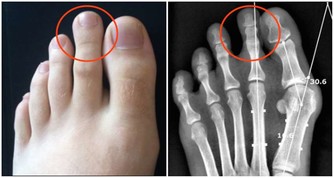

• 脊椎“變形”:當人趴著睡時,脊椎被迫彎成“C”字型,從而使腰椎、胸椎、頸椎呈非正常的生理曲度,這樣不僅會造成腰酸脖子痛,時間久了還可能誘發頸椎病、椎間盤突出。